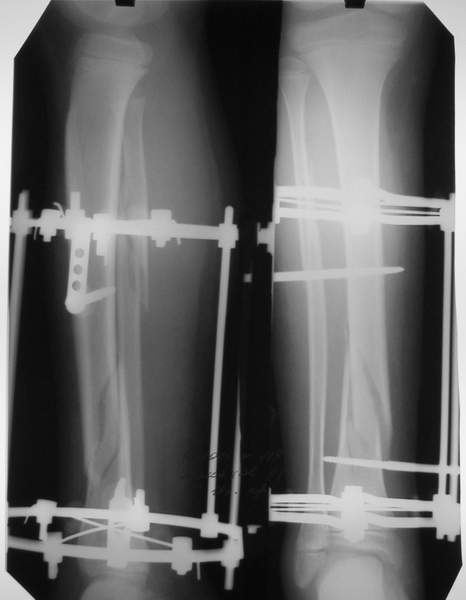

В аттачтах №№ 1 и 2 - примеры, когда 2 кольца не позволили послеоперационно

исправить смещение фрагментов большеберцовой (по ширине и вальгусное).

А казалось бы (#2) - поиграй на штангах и все влетит.

Оперировал не я

:-)